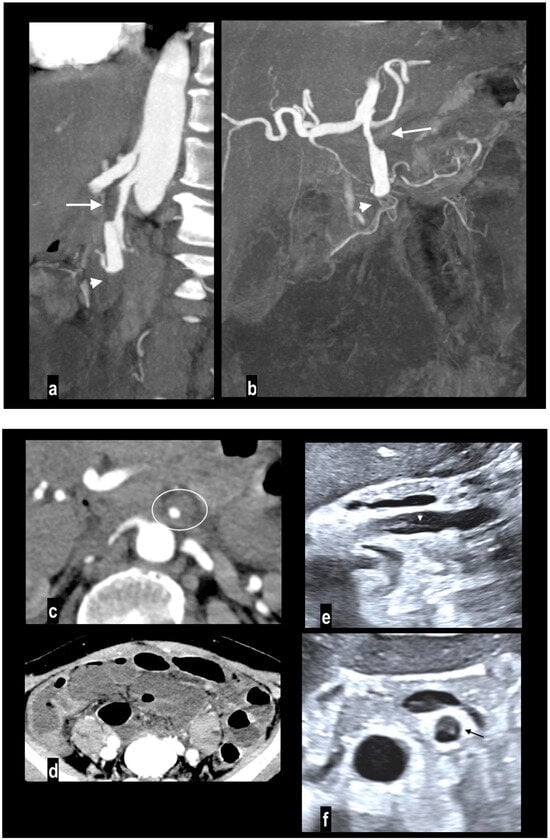

Figure 5.

SMA dissection in a 42-year-old woman. MIP arterial images (a,b) showed segmentary false lumen thrombosis in the proximal convex side of SMA, with lumen narrowing (arrow). The vessel caliber had increased ((c) oval). Distally, the intimal flap continued in a complete vessel thrombosis (arrowhead), determining bowel ischemia with hypoenhancing paper-thin bowel walls (d). Proximal false lumen thrombosis (arrow) and intimal flap (arrowhead) were also well depicted at ultrasound examination performed before MDCT (e,f). The patient underwent surgical resection of necrotic loops.